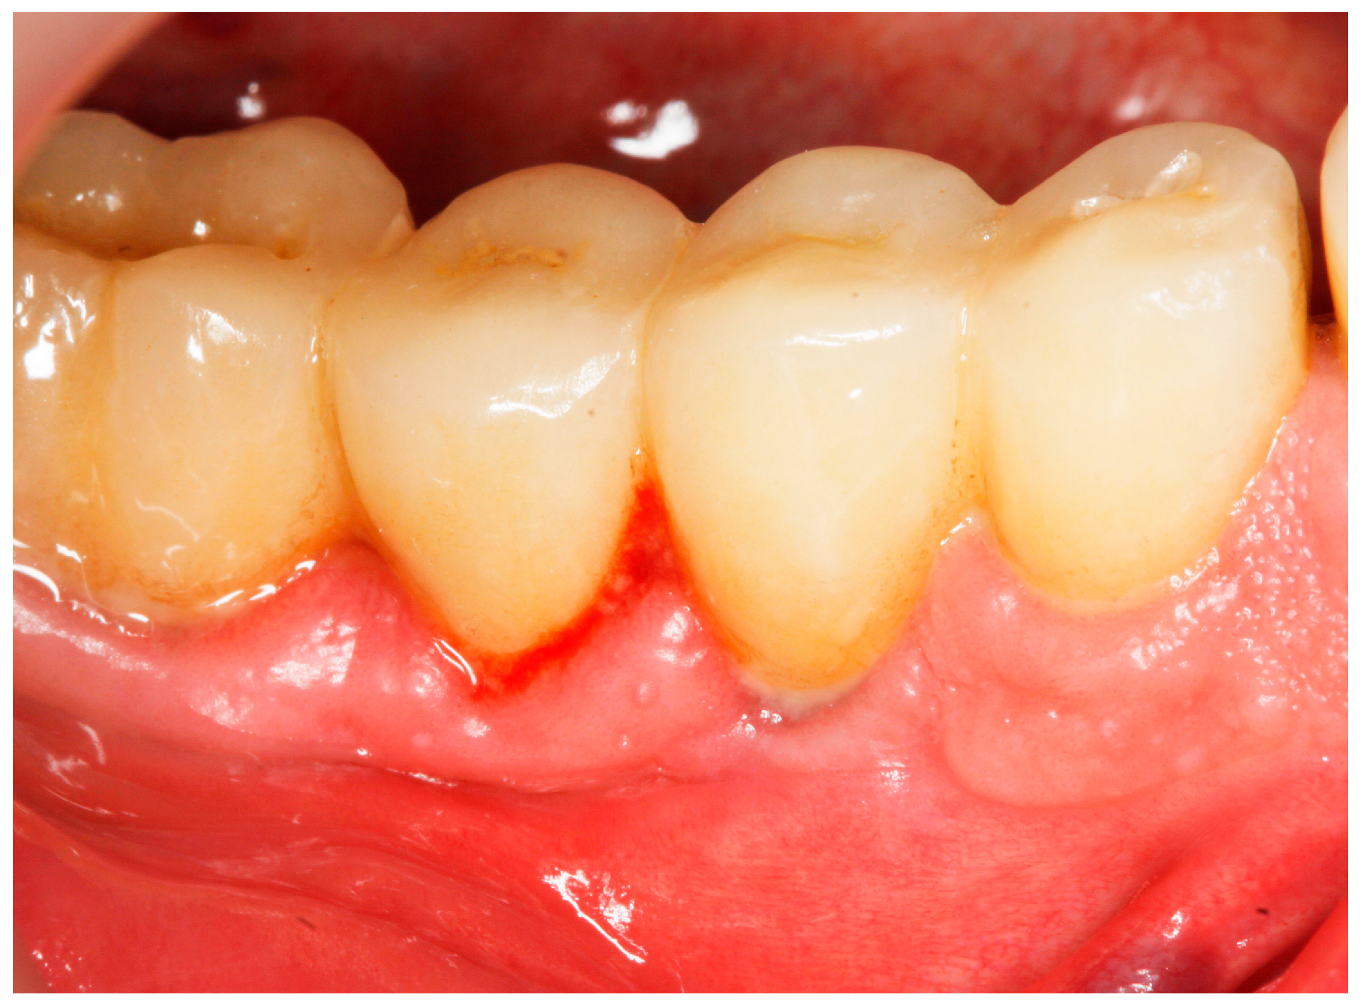

2.8. Treatment Procedures

- PMPR, individualized OH recommendations, for entire dentition/implants;